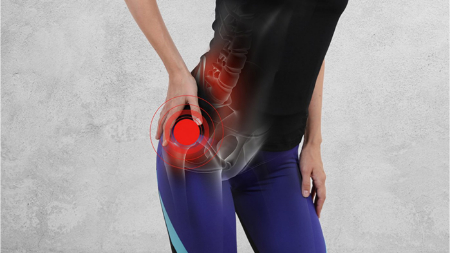

درد باسن و لگن؟ مقصران احتمالی و راه های رهایی

چه چیزی باعث درد باسن شما می شود؟ راهنمای تشخیص و درمان

هر لگن خاصره یک مفصل توپی-حفره ای است. توپ، قسمت بالایی استخوان ران (سر فمور) است. حفره (استابولوم) در استخوان لگن شما قرار دارد. بافت صاف و لغزنده ای به نام غضروف به توپ و حفره اجازه می دهد تا هنگام حرکت روی هم بلغزند. یک پوشش نازک (سینوویوم) روی غضروف قرار گرفته و کمی مایع سینوویال تولید می کند که باعث کاهش بیشتر اصطکاک می شود. تاندون ها، رباط ها و عضلات مفصل را کامل می کنند.

درد باسن یا لگن می تواند ناشی از عوامل مختلفی باشد، از جمله مشکلات مربوط به مفاصل، عضلات، استخوان ها و اعصاب. این درد می تواند تیز، مبهم، سوزان یا دردناک باشد و ممکن است در ناحیه لگن، ران، کشاله ران یا باسن احساس شود.